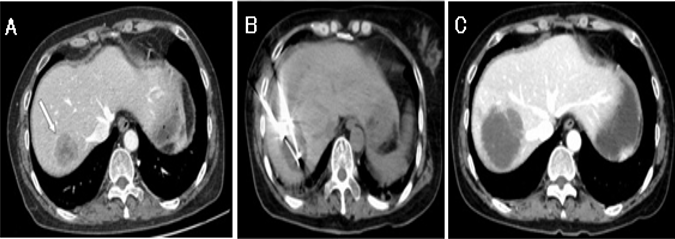

Figura 6: A: imagen en fase portal de TC con lesión de baja atenuación. B: Imagen de la TC sin contraste durante la crioablación.

El parénquima hepático adyacente mostró un cambio de baja densidad durante el ciclo de congelación.

C: TC de seguimiento sin realce del contraste de la lesión, que sugiere una remisión completa.